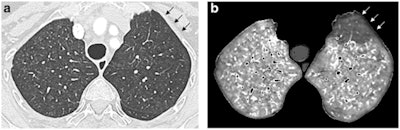

Dual-energy CT angiographic examination obtained in an 85-year-old female with limited cutaneous systemic sclerosis diagnosed 18 years earlier (159 cm, 60 kg), precapillary pulmonary hypertension recognized four years before this exam, and suspicion of pulmonary veno-occlusive disease or pulmonary capillary hemangiomatosis. Paired lung and perfusion images obtained at the level of the upper lobes (a, b), showing profuse, ill-defined lung micronodules in both lungs (a), highly suggestive of pulmonary veno-occlusive disease or pulmonary capillary hemangiomatosis, and a pulmonary embolism-type perfusion defect in the anterior segment of the left upper lobe (arrows, b). This perfusion defect was the only perfusion defect, seen in the absence of CT features of acute and/or chronic pulmonary embolism.The Lille team found that 37 patients had no systemic sclerosis-related lung involvement (group A). Another 56 patients had systemic sclerosis-related interstitial lung disease (group B) of variable extent (group B mild, ≤ 10% of lung parenchyma involved, n = 17; group B moderate: between 11% and 50%, n = 31; group B severe, > 50%, n = 8). Eight patients had pulmonary veno-occlusive disease or pulmonary capillary hemangiomatosis (group C).